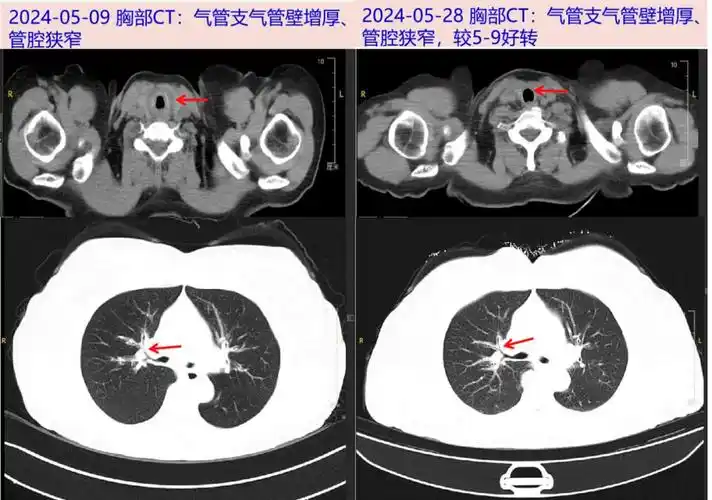

五,最后诊断与诊断依据最终诊断复发性多软骨炎(累及气管,甲状软骨